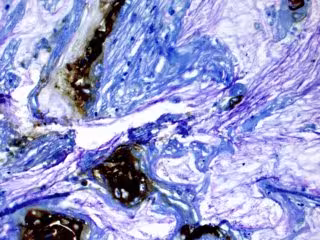

Las áreas marrones se tiñen para un biomarcador en el tejido de un paciente que desarrolló cáncer de páncreas a partir de un quiste.

Las áreas marrones se tiñen para un biomarcador en el tejido de un paciente que desarrolló cáncer de páncreas a partir de un quiste. - KOUSHIK DAS, MD - Archivo